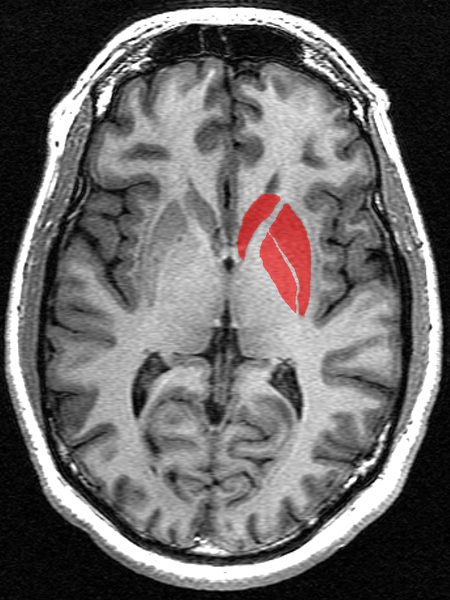

Salute Riconosciuto un nuovo ruolo per i segnali sensoriali nel cervello La scoperta potrebbe portare a benefici per i pazienti affetti da Parkinson o…MIT Technology Review Italia26/04/2019